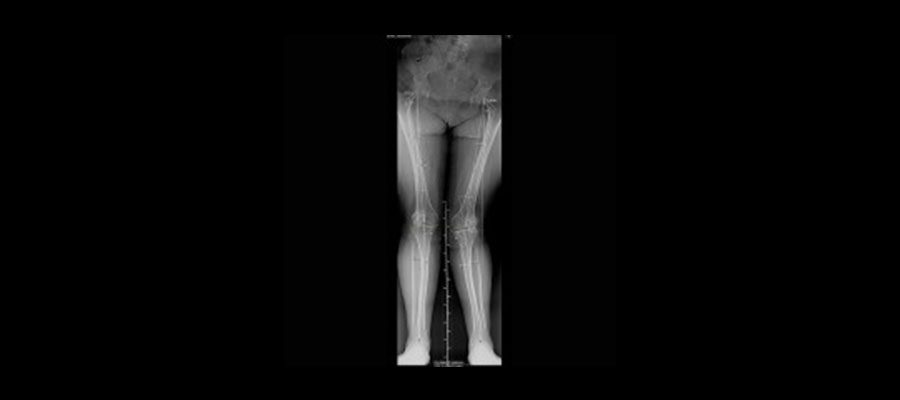

Ortoröntgenogram, skolyoz filmi olarak da bilinir. Bu çekim yapılırken röntgen cihazlarından yardım alınır. Skolyoz filmi çekilirken hastanın ayakta durması gerekir. Çekimden maksimum  verimi alabilmek için hem ön hem de arka açıdan çekim yapılır. Bu şekilde omurga ve bel detaylı şekilde görüntülenir. Çekim yapılırken hasta üzerindeki tüm metalleri çıkartır ve ardından ayakta sabit şekilde durur. Bu esnada röntgen cihazı yardımıyla çekim yapılır.

Röntgen cihazları kullanılarak yapılan Ortoröntgenogram çekimi her iki açıdan da yapılır ve omurga detaylı şekilde görüntülenir. Oldukça kısa süren ve ağrısız olan bu çekim sayesinde kolayca skolyoz tespiti yapılır. Yaklaşık 15 dakika süren Ortoröntgenogram çekimi esnasında hasta hiç acı hissetmez.